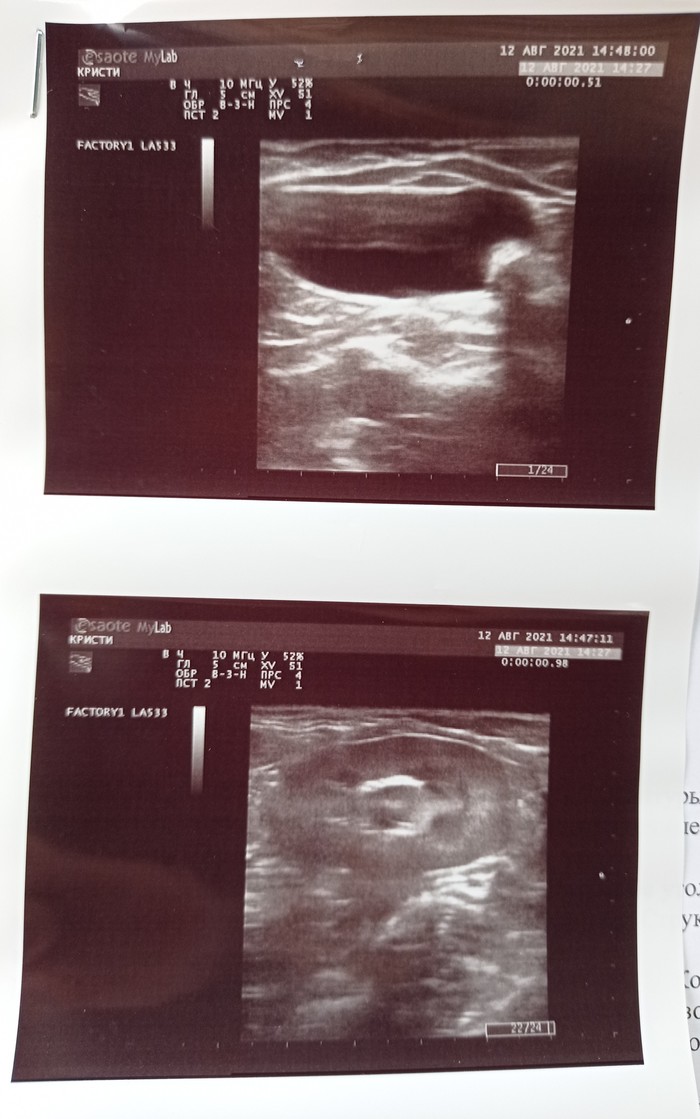

Перед операцией назначается рутинное обследование - анализы крови + ЭХО сердца для выявления скрытых патологий и оценки анестезиологических рисков. Взвешиваются все за и против и в зависимости от результатов животное может пойти на операцию, пойти дообследоваться и лечиться или никуда не пойти (давайте честно, если у бобика сердце квадратное и ему жить осталось два понедельника нет особого смысла ему чистить камешки с зубов).